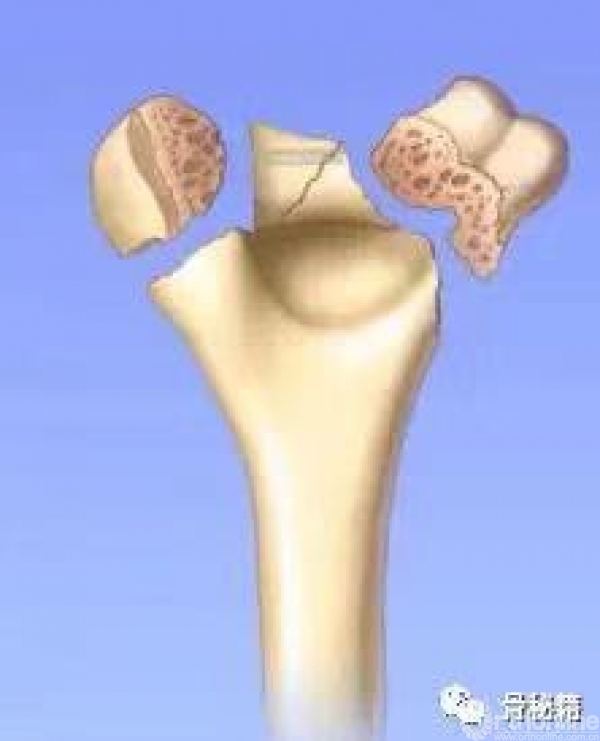

1.复位时,先把滑车固定好,可应用空心螺钉。

2.然后用克氏针将骨折块经过钢板来进行固定,注意钢板一定要把远端包裹一点。

1.最大限度地固定远端碎片。

2.确保远端节段的所有固定有助于提高髁间水平的稳定性。

6.螺钉应通过交叉锁定在一起,从而形成角稳定结构并将内外侧柱连接在一起。